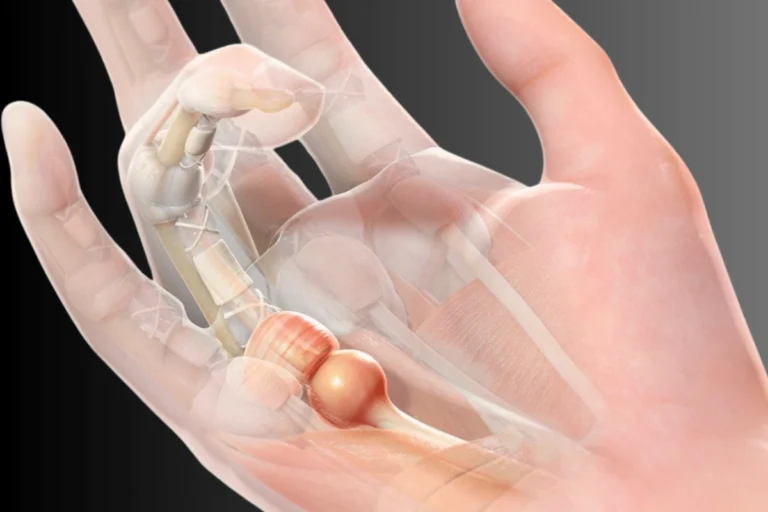

Trigger Finger

What is Trigger Finger?

Trigger finger occurs when the tendon in the finger becomes inflamed, causing the finger to lock or catch when bending or straightening.

Treatment

Minimally invasive injections can reduce tendon inflammation and restore smooth finger movement.

Common Symptoms

Finger stiffness

Pain in the palm

Clicking or locking sensation

Difficulty straightening the finger